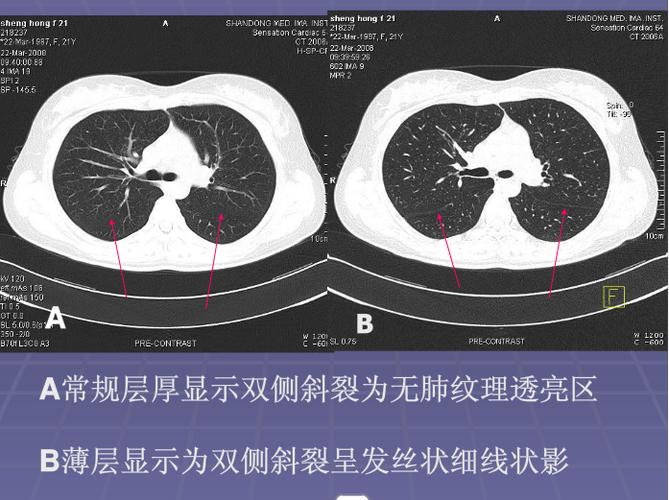

正常肺CT肺窗示意图

正常肺CT肺窗示意图,正常肺CT肺窗示意图